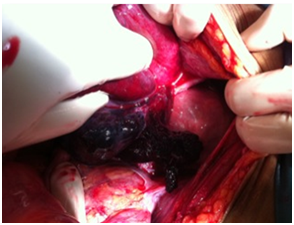

A 29-year-old lady, without significant medical history, presented to our hospital emergency department with 3 days history of constipation associated with generalized abdominal pain, nausea and vomiting. On further history taking, patient had a traditional massage done due to lower abdominal pain. On examination, the abdomen was distended with diffuse marked tenderness without rigidity or guarding; no hernias or masses were noted, bowel sound was sluggish. Digital rectal examination reveal normal finding. We proceeded with imaging. Abdomen X-ray shows large bowel loops are dilatation measuring about 6cm and an ultrasound abdomen was done and there were free fluid presence in the abdomen and pelvis. Our impression on that time was perforated appendicitis. We proceeded with exploratory laparotomy and the intraoperative findings shows gangrenous sigmoid colon secondary to volvulus caused by broad ligament tear and twisted left ovarian cyst. We proceeded with a Hartmann's procedures. Post operative was uneventful and patient was discharge home at day five post operation (Figures 1–4).

Figure 2 Intraoperative findings revealing sigmoid volvulus.

Figure 3 Intraoperative finding shows part of the redundant sigmoid colon gangrene.

Figure 4 Intraoperative finding shows part of the redundant sigmoid colon gangrene that enters through a tear at the broad ligament and become volvulus with torsion of the left ovary.